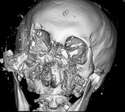

附圖

>>29009604

被熊巴臉的斷層掃描是這樣

>>29009661

哇幹人類就像玩具一樣脆弱

哇幹 一般人一掌下去變島民w